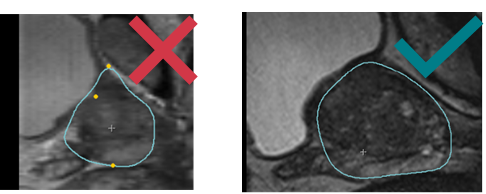

During the MRI/US fusion, on the axial and sagittal views, US and MRI prostate contours are not continuous and don't seem to be the same prostate image.

- Make sure the blue contour fits correctly with the prostate shape on MRI & US: